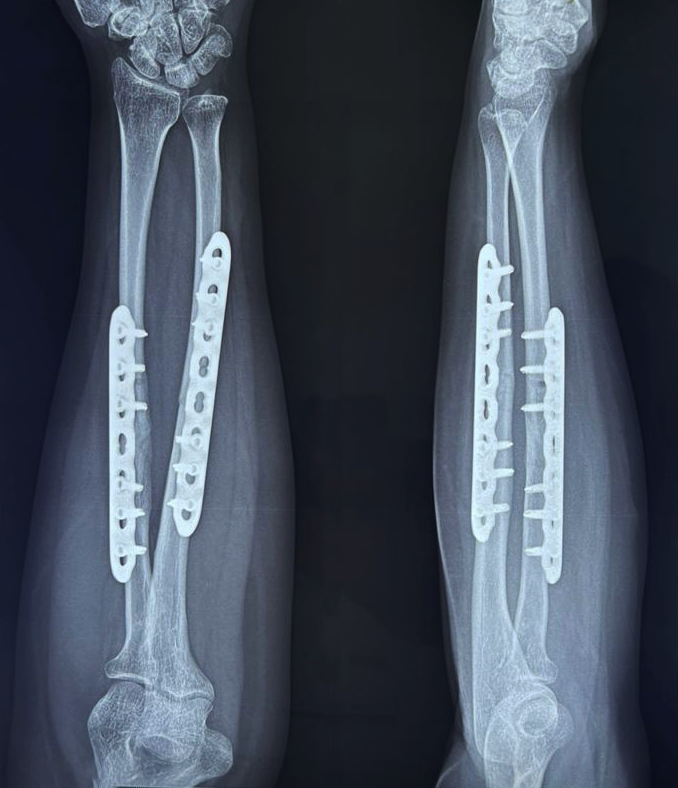

- Fracture Treatment: We specialize in the surgical and non-surgical treatment of

fractures, utilizing advanced techniques to ensure optimal healing and recovery.

- Expertise in Trauma Care: Dr. Zambare is highly skilled in managing complex trauma

cases, including multi-limb injuries and severe fractures. His expertise ensures that patients receive

precise and effective treatment for their injuries.